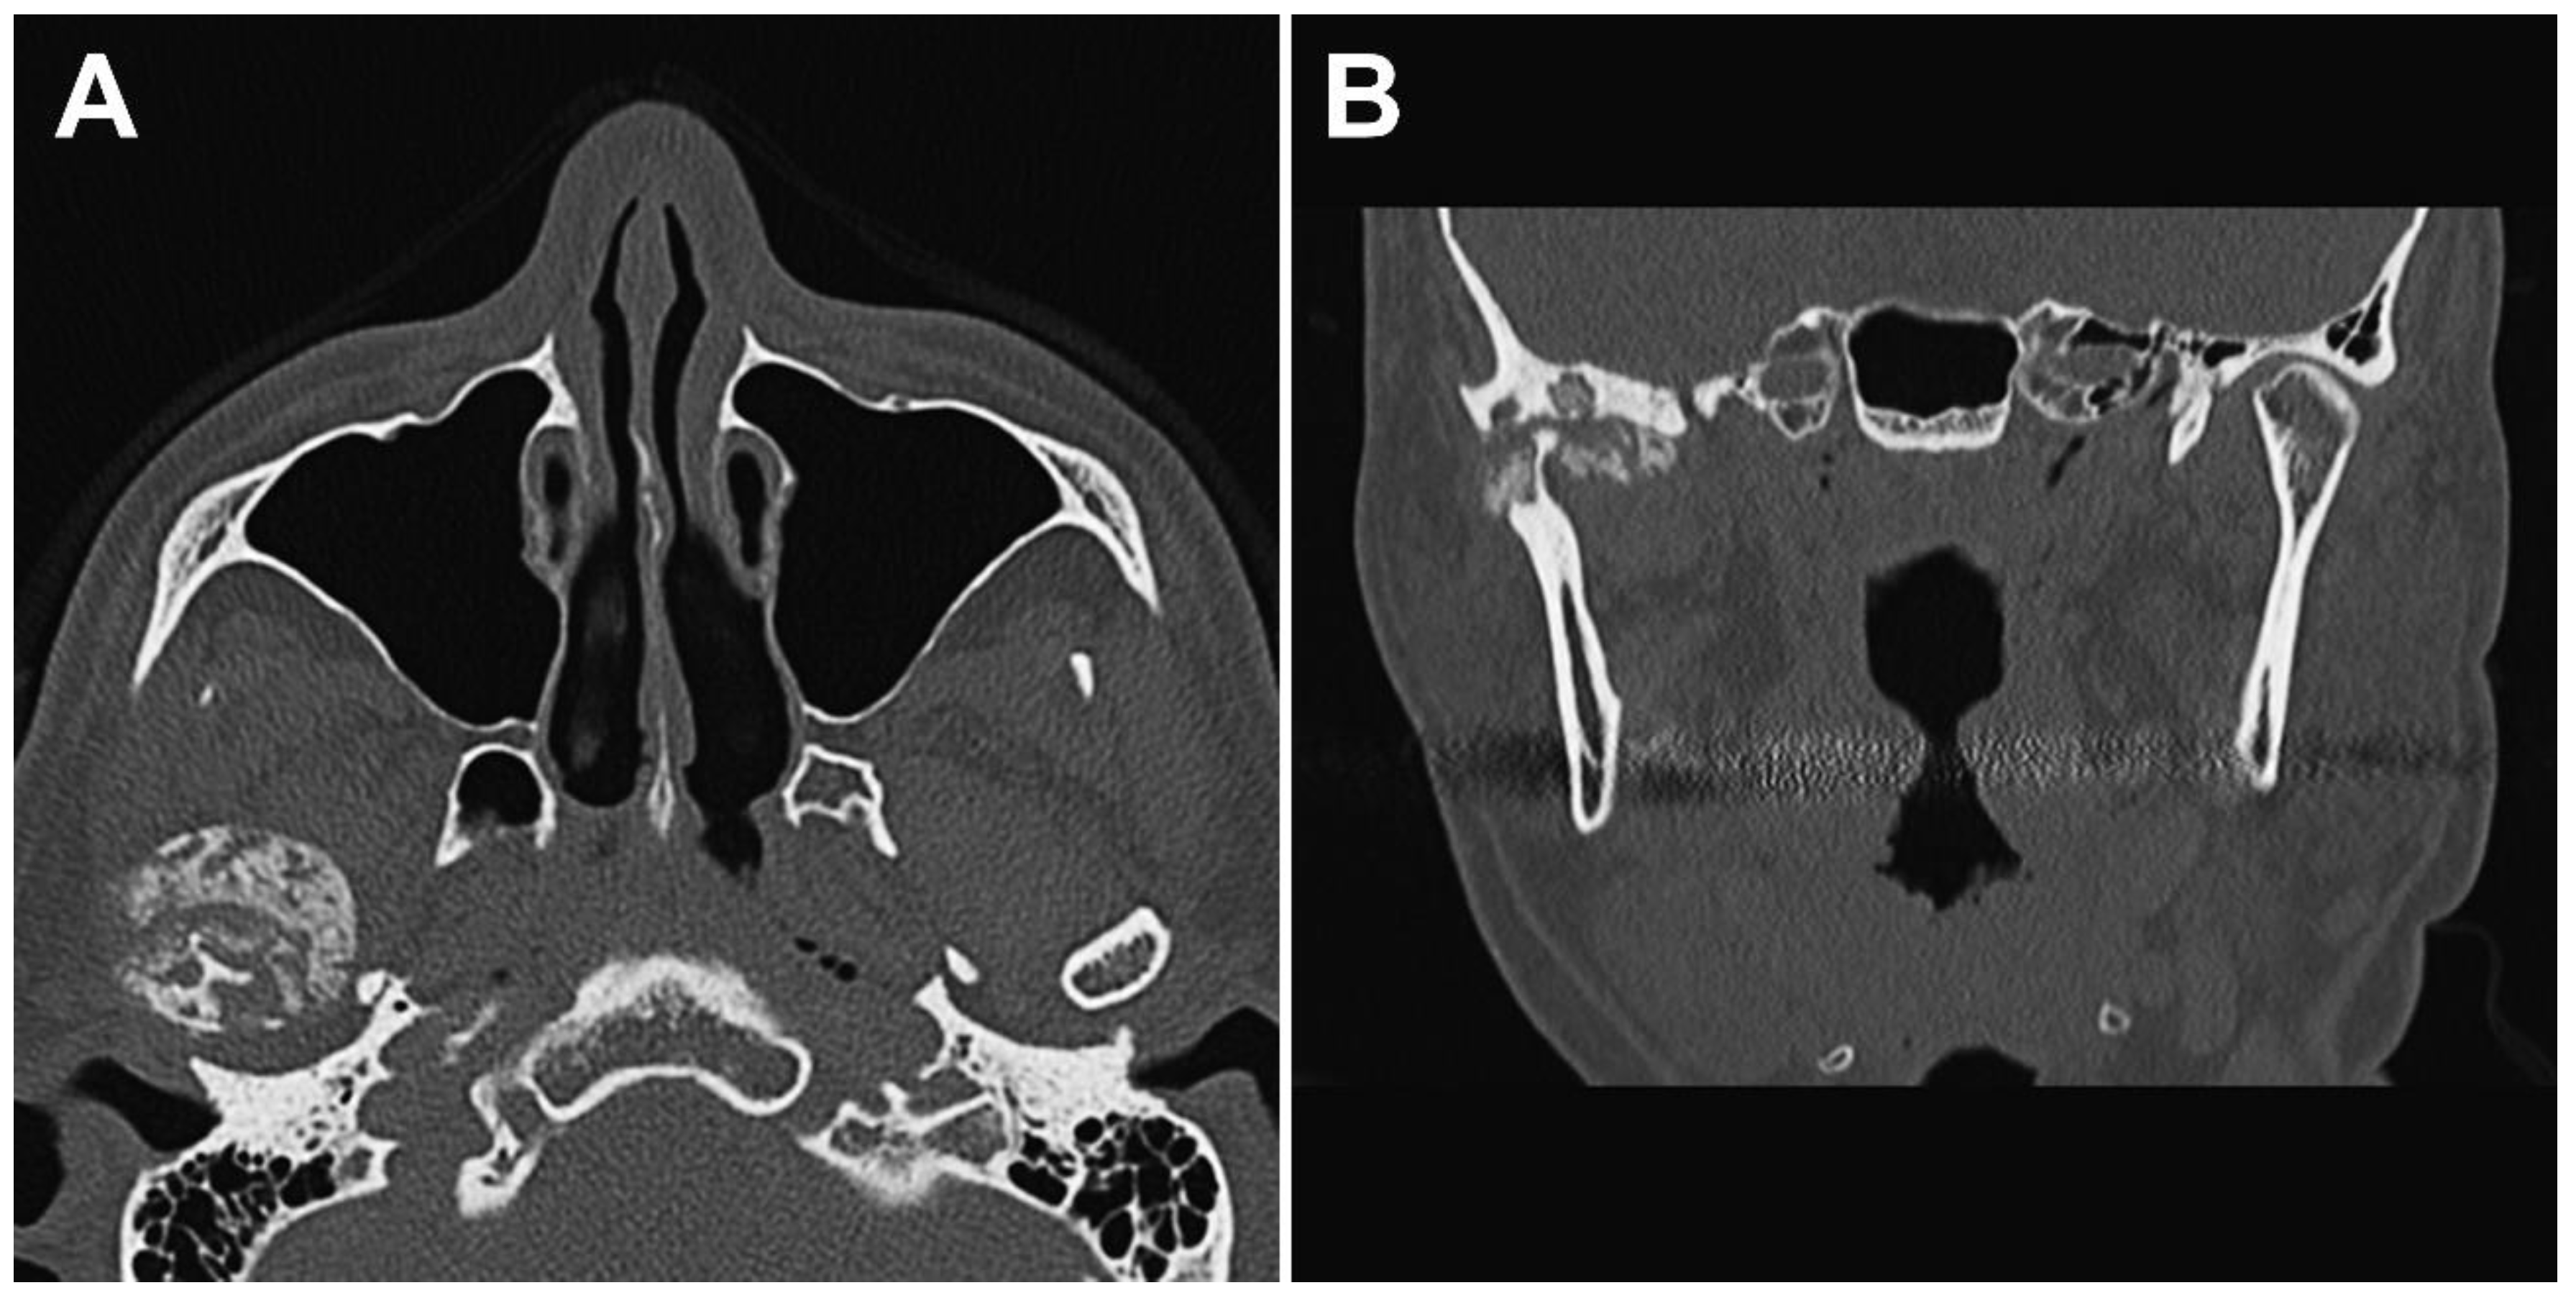

Figure 2.

Preoperative computed tomography (CT) images. (A) Axial CT images showing the intra-articular localized, non-corticated, and ill-marginated calcified lesion that abuts the articular surface of the glenoid fossa around the right mandibular condyle. (B) Coronal CT images of the right temporomandibular joint revealed resorption of part of the mandibular condyle and cranial base.

The panoramic radiograph showed an unclear right mandibular condyle with a cloud-like mass (Figure 1). Computed tomography (CT) revealed that the right mandibular condyle was destroyed, and that mottled-like hard tissues had formed around the condyle as viewed on the axial plane (Figure 2A). Similarly, it was confirmed on the coronal plane that the mandibular fossa and cranial base were destroyed. Furthermore, calcified opacity was observed in the bone resorption fossa (Figure 2B). Proton density-weighted imaging showed no disc dislocation in the right TMJ, and the area corresponding to the upper and lower joint space was filled with uneven hypointensity, and the joint space appeared dilated. Additionally, the high signal inside and granular low-signal images were scattered inside the mandibular condyle and fossa (Figure 3). The left TMJ showed no abnormal findings. Based on these findings, we suspected CPPD deposition disease as a clinical diagnosis and excised the lesion under general anesthesia. The right TMJ was exposed using a preauricular approach. During surgery, we confirmed and removed the white chalk-like masses (Figure 4). These masses were present in the articular capsule, articular eminence, mandibular condyle, the upper and lower joint cavities, and articular disc. The maximum size of the masses was 16 × 5 × 5 mm, although various sizes were extracted. CT images were obtained after surgery, and we confirmed that the masses were extracted from the right temporomandibular joint (Figure 5). The postoperative healing was uneventful. This was six months post-surgery, and although the pain in the right TMJ was persistent when opening the mouth, the maximal mouth opening had improved to 42 mm.